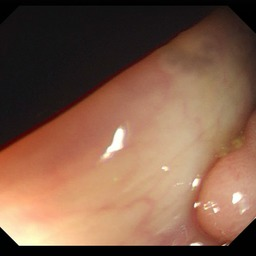

Medical image segmentation is a primary task in many applications, and the accuracy of the segmentation is a necessity. Recently, many deep learning networks derived from U-Net have been extensively used and have achieved notable results. To further improve and refine the performance of U-Net, parallel decoders along with mask prediction decoder have been carried out and have shown significant improvement with additional advantages. In our work, we utilize the advantages of using a combination of contour and distance map as regularizers. In turn, we propose a novel architecture Psi-Net with a single encoder and three parallel decoders, one decoder to learn the mask and other two to learn the auxiliary tasks of contour detection and distance map estimation. The learning of these auxiliary tasks helps in capturing the shape and boundary. We also propose a new joint loss function for the proposed architecture. The loss function consists of a weighted combination of Negative likelihood and Mean Square Error loss. We have used two publicly available datasets: 1) Origa dataset for the task of optic cup and disc segmentation and 2) Endovis segment dataset for the task of polyp segmentation to evaluate our model. We have conducted extensive experiments using our network to show our model gives better results in terms of segmentation, boundary and shape metrics.